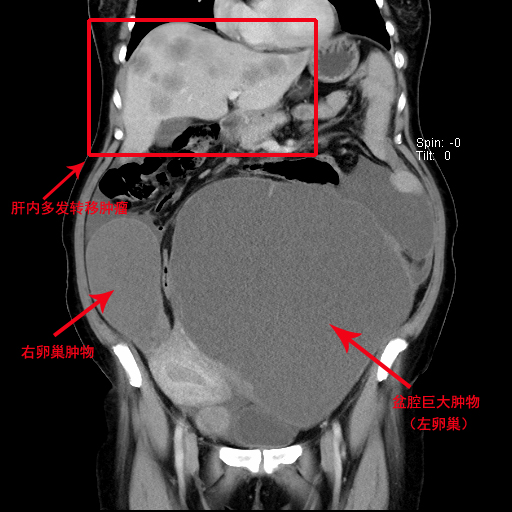

40多岁的吴女士(化名)因腹围明显增大、进食后腹胀等症状来到潞河医院妇科门诊就诊。经妇科主任高洁检查发现,吴女士全腹膨隆,腹部可触及巨大囊实性肿物,大小约40×30×30厘米。影像学检查提示腹盆腔内巨大囊实性包块,并伴有肝内多发转移瘤、大网膜结节及腹盆腔积液,考虑为晚期卵巢癌。此外,吴女士长期便秘,既往有剖宫产史及开腹手术史,进一步增加了手术难度和风险。

经过综合考虑患者意愿和实际情况后,最终决定进行开腹肿瘤细胞减灭术。手术由高洁带领妇科团队主导,普外科李若凡主任医师协助完成。术中发现患者腹盆腔被巨大囊实性肿物占据,广泛粘连,解剖结构不清,手术难度极大。术者们凭借丰富的临床经验和高超技术,逐步分离肿物与周围组织的粘连,并通过巧妙的荷包缝合技术减少囊液外渗风险,成功吸出囊液约5600毫升。整个手术历时4个多小时,最终顺利完成了全子宫切除术、双侧附件切除术、大网膜切除术、淋巴结切除术、肠粘连松解术等多项复杂操作。

术后,吴女士接受了静脉营养支持、抗炎、纠正贫血等一系列对症治疗,身体状况逐渐好转。术后第9天,吴女士的体重由前81公斤降至术后稳定的68公斤,腹部平软,排气排便正常,压迫症状完全解除。病理结果显示左侧卵巢透明细胞癌IV期,结合免疫组化分析进一步明确了诊断,后续需接受肝脏肿瘤介入治疗、辅助化疗、靶向治疗等进一步综合治疗。